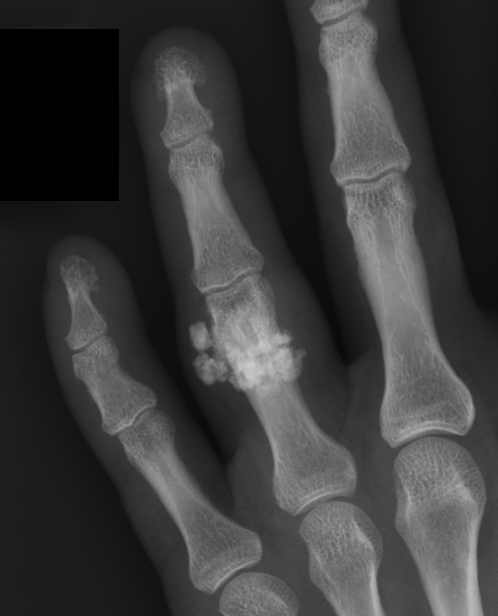

X-ray

Well defined bony mass arising from the surface of the bone

- no medulla